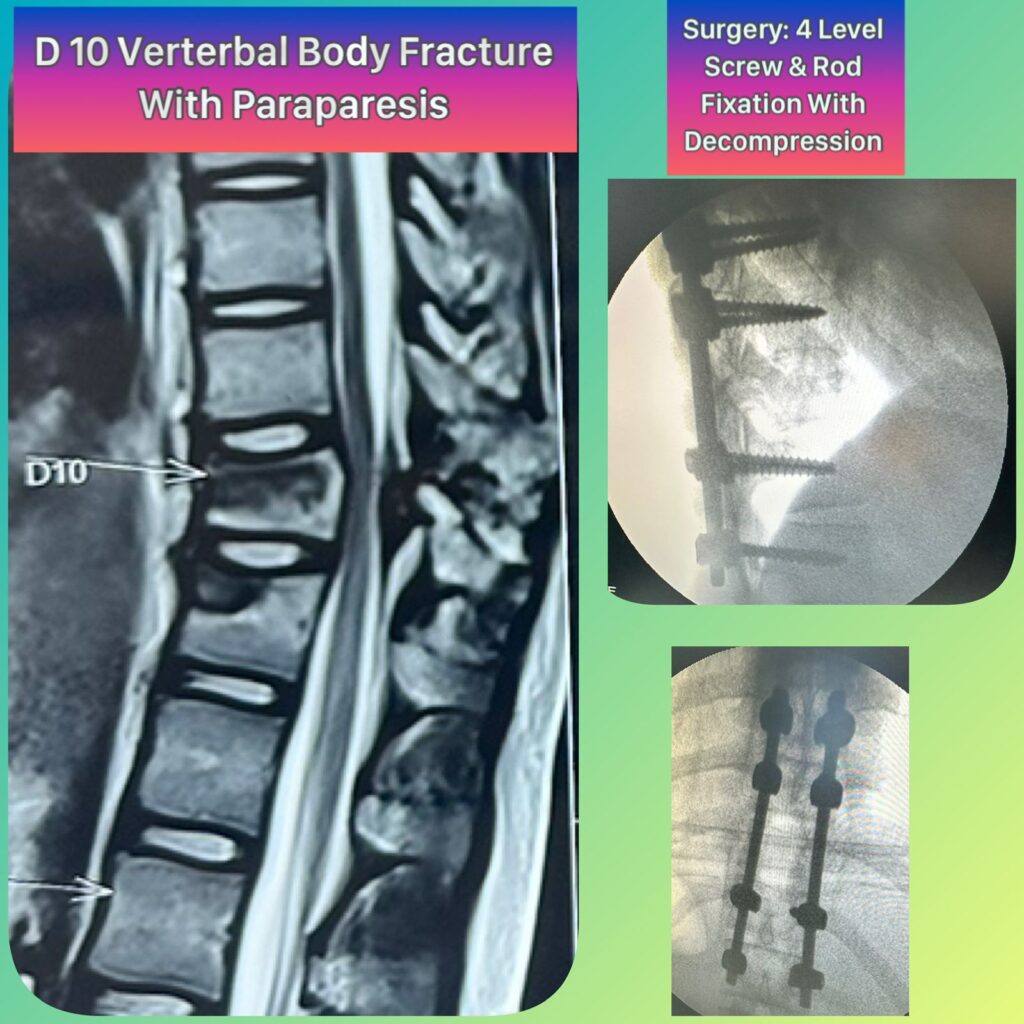

He specializes in back pain, slip disc, sciatica, and complex spine and brain disorders, with a strong focus on conservative treatment, minimally invasive surgery, and ethical, patient-centered care.